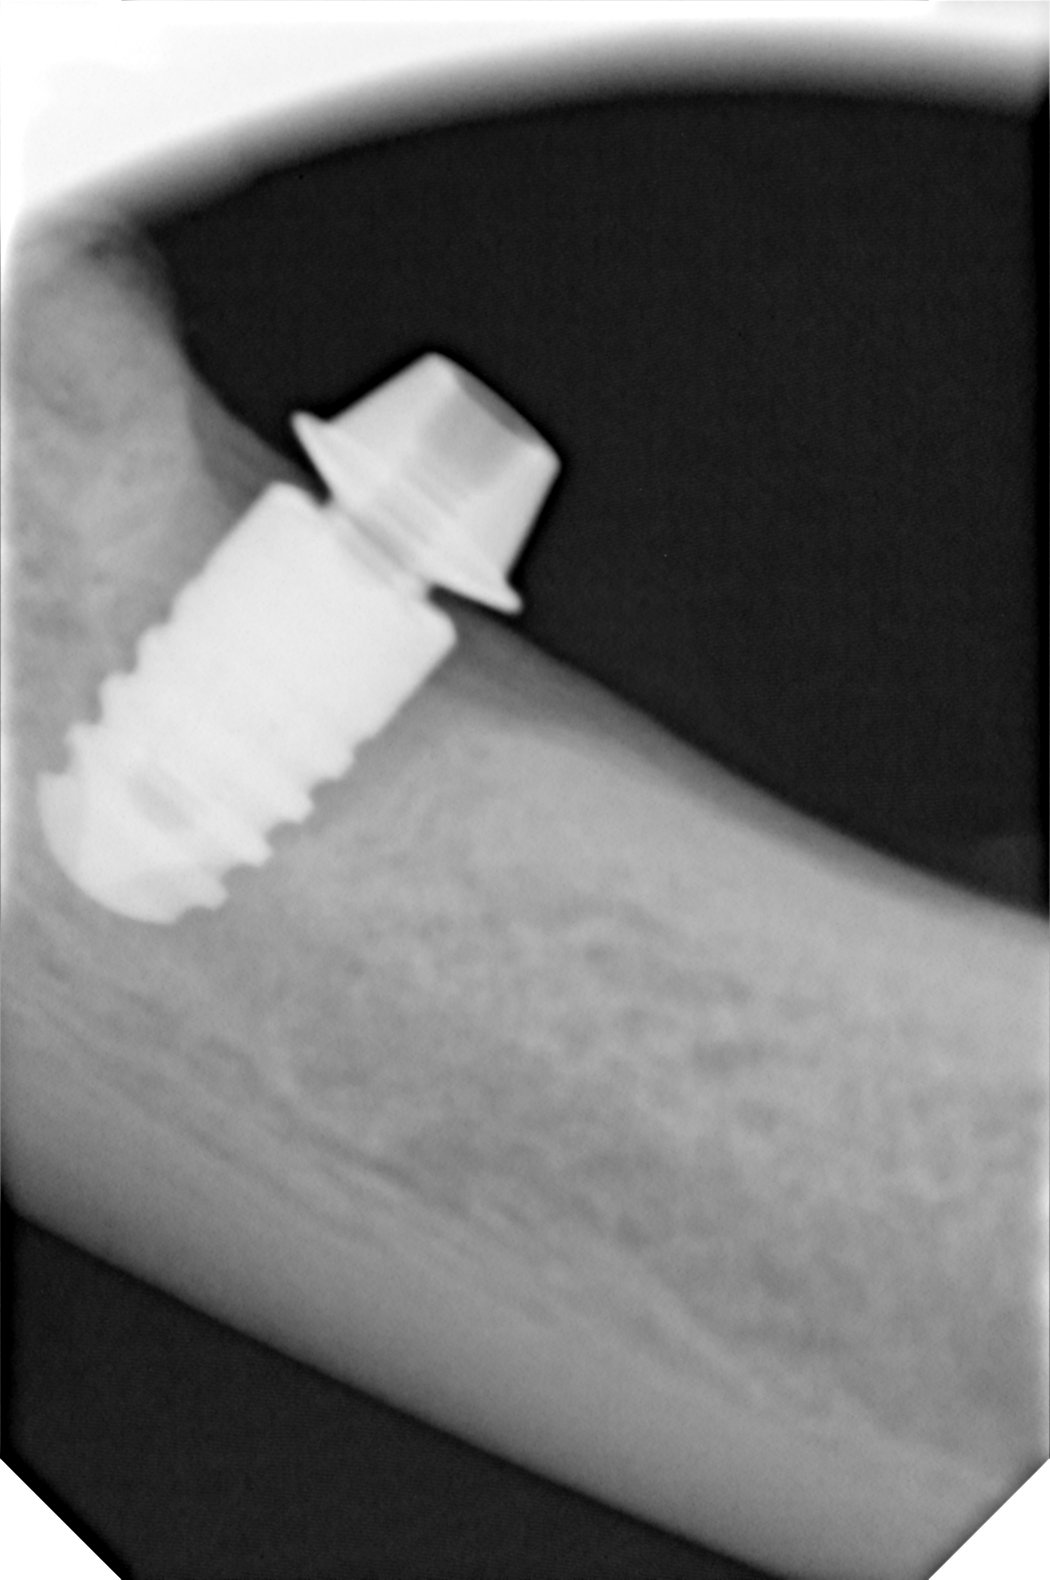

Hola. Alguien puede decirme que implante puede ser este? . Se lo pusieron a una paciente de idental hace 3 meses y la corona de Zirconio dice que ya se [...]

Que implante es???